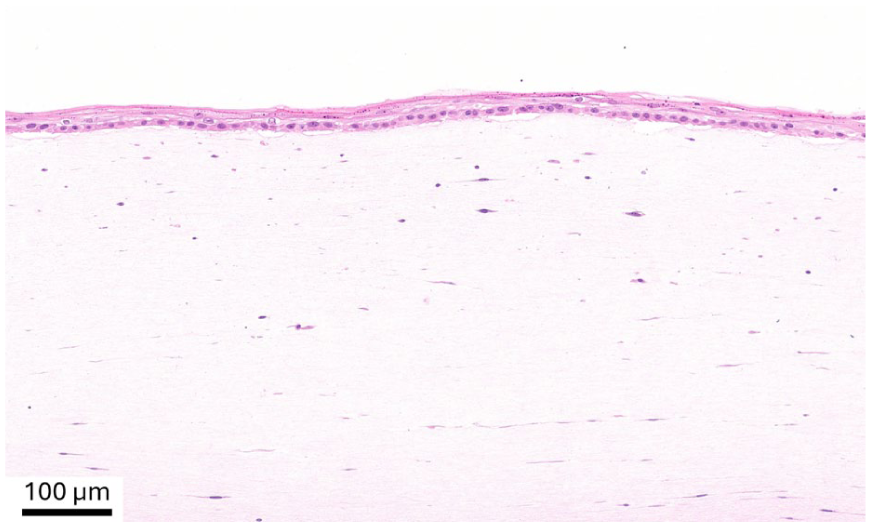

Histological analysis (H&E staining) of the construct denovoSkin™ prior to transplantation.

This study addresses several strengths and limitations. The intra-patient design allowed for direct comparison of the two treatment modalities under nearly identical wound environments, minimizing inter-subject variability. The long-term follow up and quantitative outcome evaluations in a multicenter trial setup are also strengths of this study, since these provide statistical power to the outcome analysis. This study also has some limitations. First, the sample size was relatively small, and although powered for the primary endpoint, it may not have been sufficient to detect smaller differences in secondary outcomes. Second, wound healing progression was assessed at predefined visits, therefore, progress between visits—for example, between day 28 and two months—may have gone unnoted, leading to the assessment of longer healing times. Nevertheless, the somewhat slower epithelialization of denovoSkin™ is likely due to the fact that it is produced submerged. Therefore, the epithelial differentiation is incomplete when applied to the wound and needs to be completed in situ after grafting (see Figure 2 for a histological image of the product prior to transplantation). In contrast, STSGs are already fully differentiated, and re-epithelialization occurs through cell migration from the edge of the meshes, resulting in faster wound closure. Also, denovoSkin™ requires neovascularization of the dermal component before full epithelization can be completed, similar to dermal templates. 33